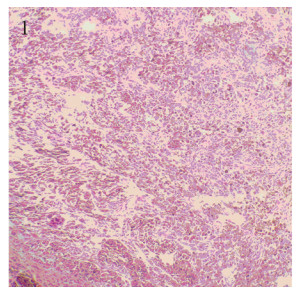

患者,男,63岁,因进食梗咽不适3月就诊。2018年6月22日胃镜病理检查:(食管距门齿37~45 cm)组织表面被覆复层鳞状上皮,间质内见梭形细胞弥漫分布,细胞异型明显,核分裂相罕见,考虑为间叶源性梭形细胞肿瘤。免疫组织化学:CK(-),CK7(-),CK20(-),p40(-),p63(-),Vimentin(+),CD34(-),Ki67 50%(+)。2018年7月9日上腹部CT示食管下段贲门、胃底占位,周围淋巴结肿大。2018年7月17日全麻下行食管下端及胃底肿物切除术,术中探查食管下段及胃底分别扪及肿瘤各约3、4 cm直径大小,周围淋巴结肿大。术后病理:(下段食道及近端胃切除根治标本)恶性黑色素瘤(图 1~2),见肿瘤两枚,位于食管下端近贲门处,大小分别为4.5 cm×3.8 cm×3.0 cm及5.0 cm×3.5 cm×2.8 cm,两者相距约3.0 cm;另送“食管贲门切缘”和“胃底切缘”未见肿瘤累及;淋巴结情况:贲门旁组2/4,小弯侧0/8,大弯侧0/5有转移;大网膜未见肿瘤累及;免疫组织化学: CK(-), CK7(-),CK20(-),CEA(-),Villin(-),p40(-),CK5/6(-),Vimentin(+), A103(+),S-100(+),HMB45(-),CK8/18(-),p53(+),Ki67 50%(+);BRAF、C-KIT基因检测未见突变。患者2013年因“左肾透明细胞癌”行左肾切除术,无高血压及糖尿病病史,否认肿瘤家族史。